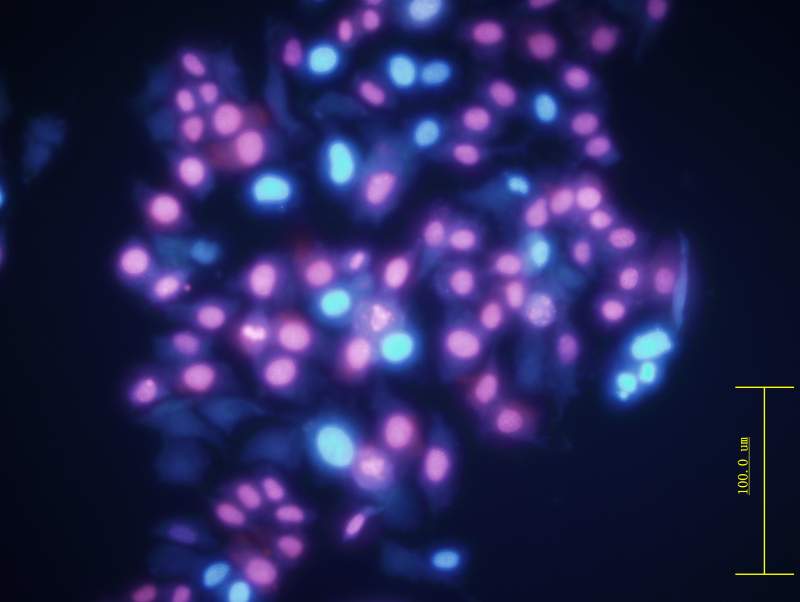

ϸ°û¾­¹ýÎïÀí½áºÏ»¯Ñ§ÁÆ·¨36 Сʱºó£¬ ÓÃhoechst Ⱦɫ ºÍPIȾɫ£¬¹Û²ìÆÚÐÎ̬¡£

ÓÐË¿·ÖÁÑÔÖÄÑ£¬ÍíÆÚµòÍö£¬»µËÀ£¿

¸ßÀ¶É«£ºµòÍöÂð£¿

Õû¸öϸ°ûµ­À¶É«£¿ÊǺËËéÁÑ¡¢ºËÈܽ⻹ÊÇhoechest ´ãÃð£¨Ï¸°ûͬʱHoechst ºÍPIȾɫ£©

ºìɫΪ»µËÀÂð£¿Õû¸öϸ°ûµ­À¶É«ÎªÊǺËËéÁÑ¡¢ºËÈܽ⻹ÊÇhoechest ´ãÃð£¨Ï¸°ûͬʱHoechst ºÍPIȾɫ£©

ºìɫΪ»µËÀÂ𣿸ßÀ¶É«ÎªµòÍö£¿

µ­À¶É«ÀïÃæ¶¼Óе­µ­µÄºìȾ£¿ÊÇʲôÇé¿ö£¿ÊÇ»µËÀºó»¹²ÐÁô×ÅDNAÎïÖÊ£¿